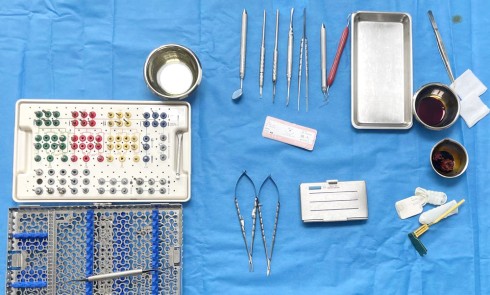

Actes préopératoires

La couronne a été déposée et une vis de couverture mise en place. La patiente a reçu un nettoyage supra-gingival général avec une attention particulière pour l’implant 47, et une irrigation locale avec du gel de chlorhexidine et du peroxyde d’hydrogène pour réduire l’inflammation des tissus. De l’amoxicilline (3 x 500 mg) a été prescrite, à commencer la veille de l’intervention chirurgicale.